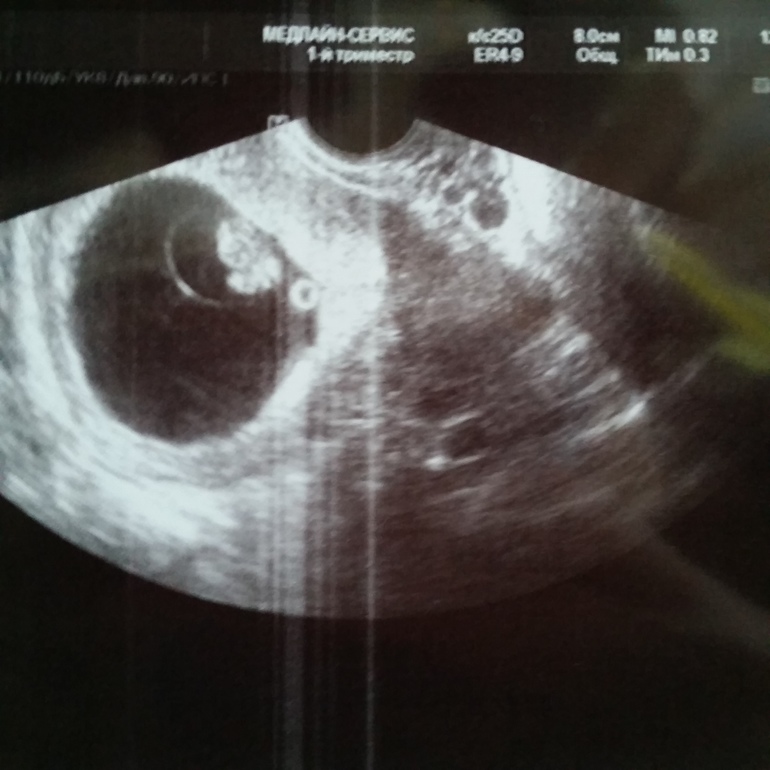

Снова УЗИ😇 8 недель

УЗИ, КТГ, доплерПривет всем! Новостей несколько: 1) я удалила наконец осколок зуба (с уколом, хотя не стоило ибо было не больно бы). 2) мы прошли ещё 1 узи и я увидела как пульсирует сердечко💖💖💖💖 мы идём четко в срок и все развивается хорошо!) Вот наша фоточка